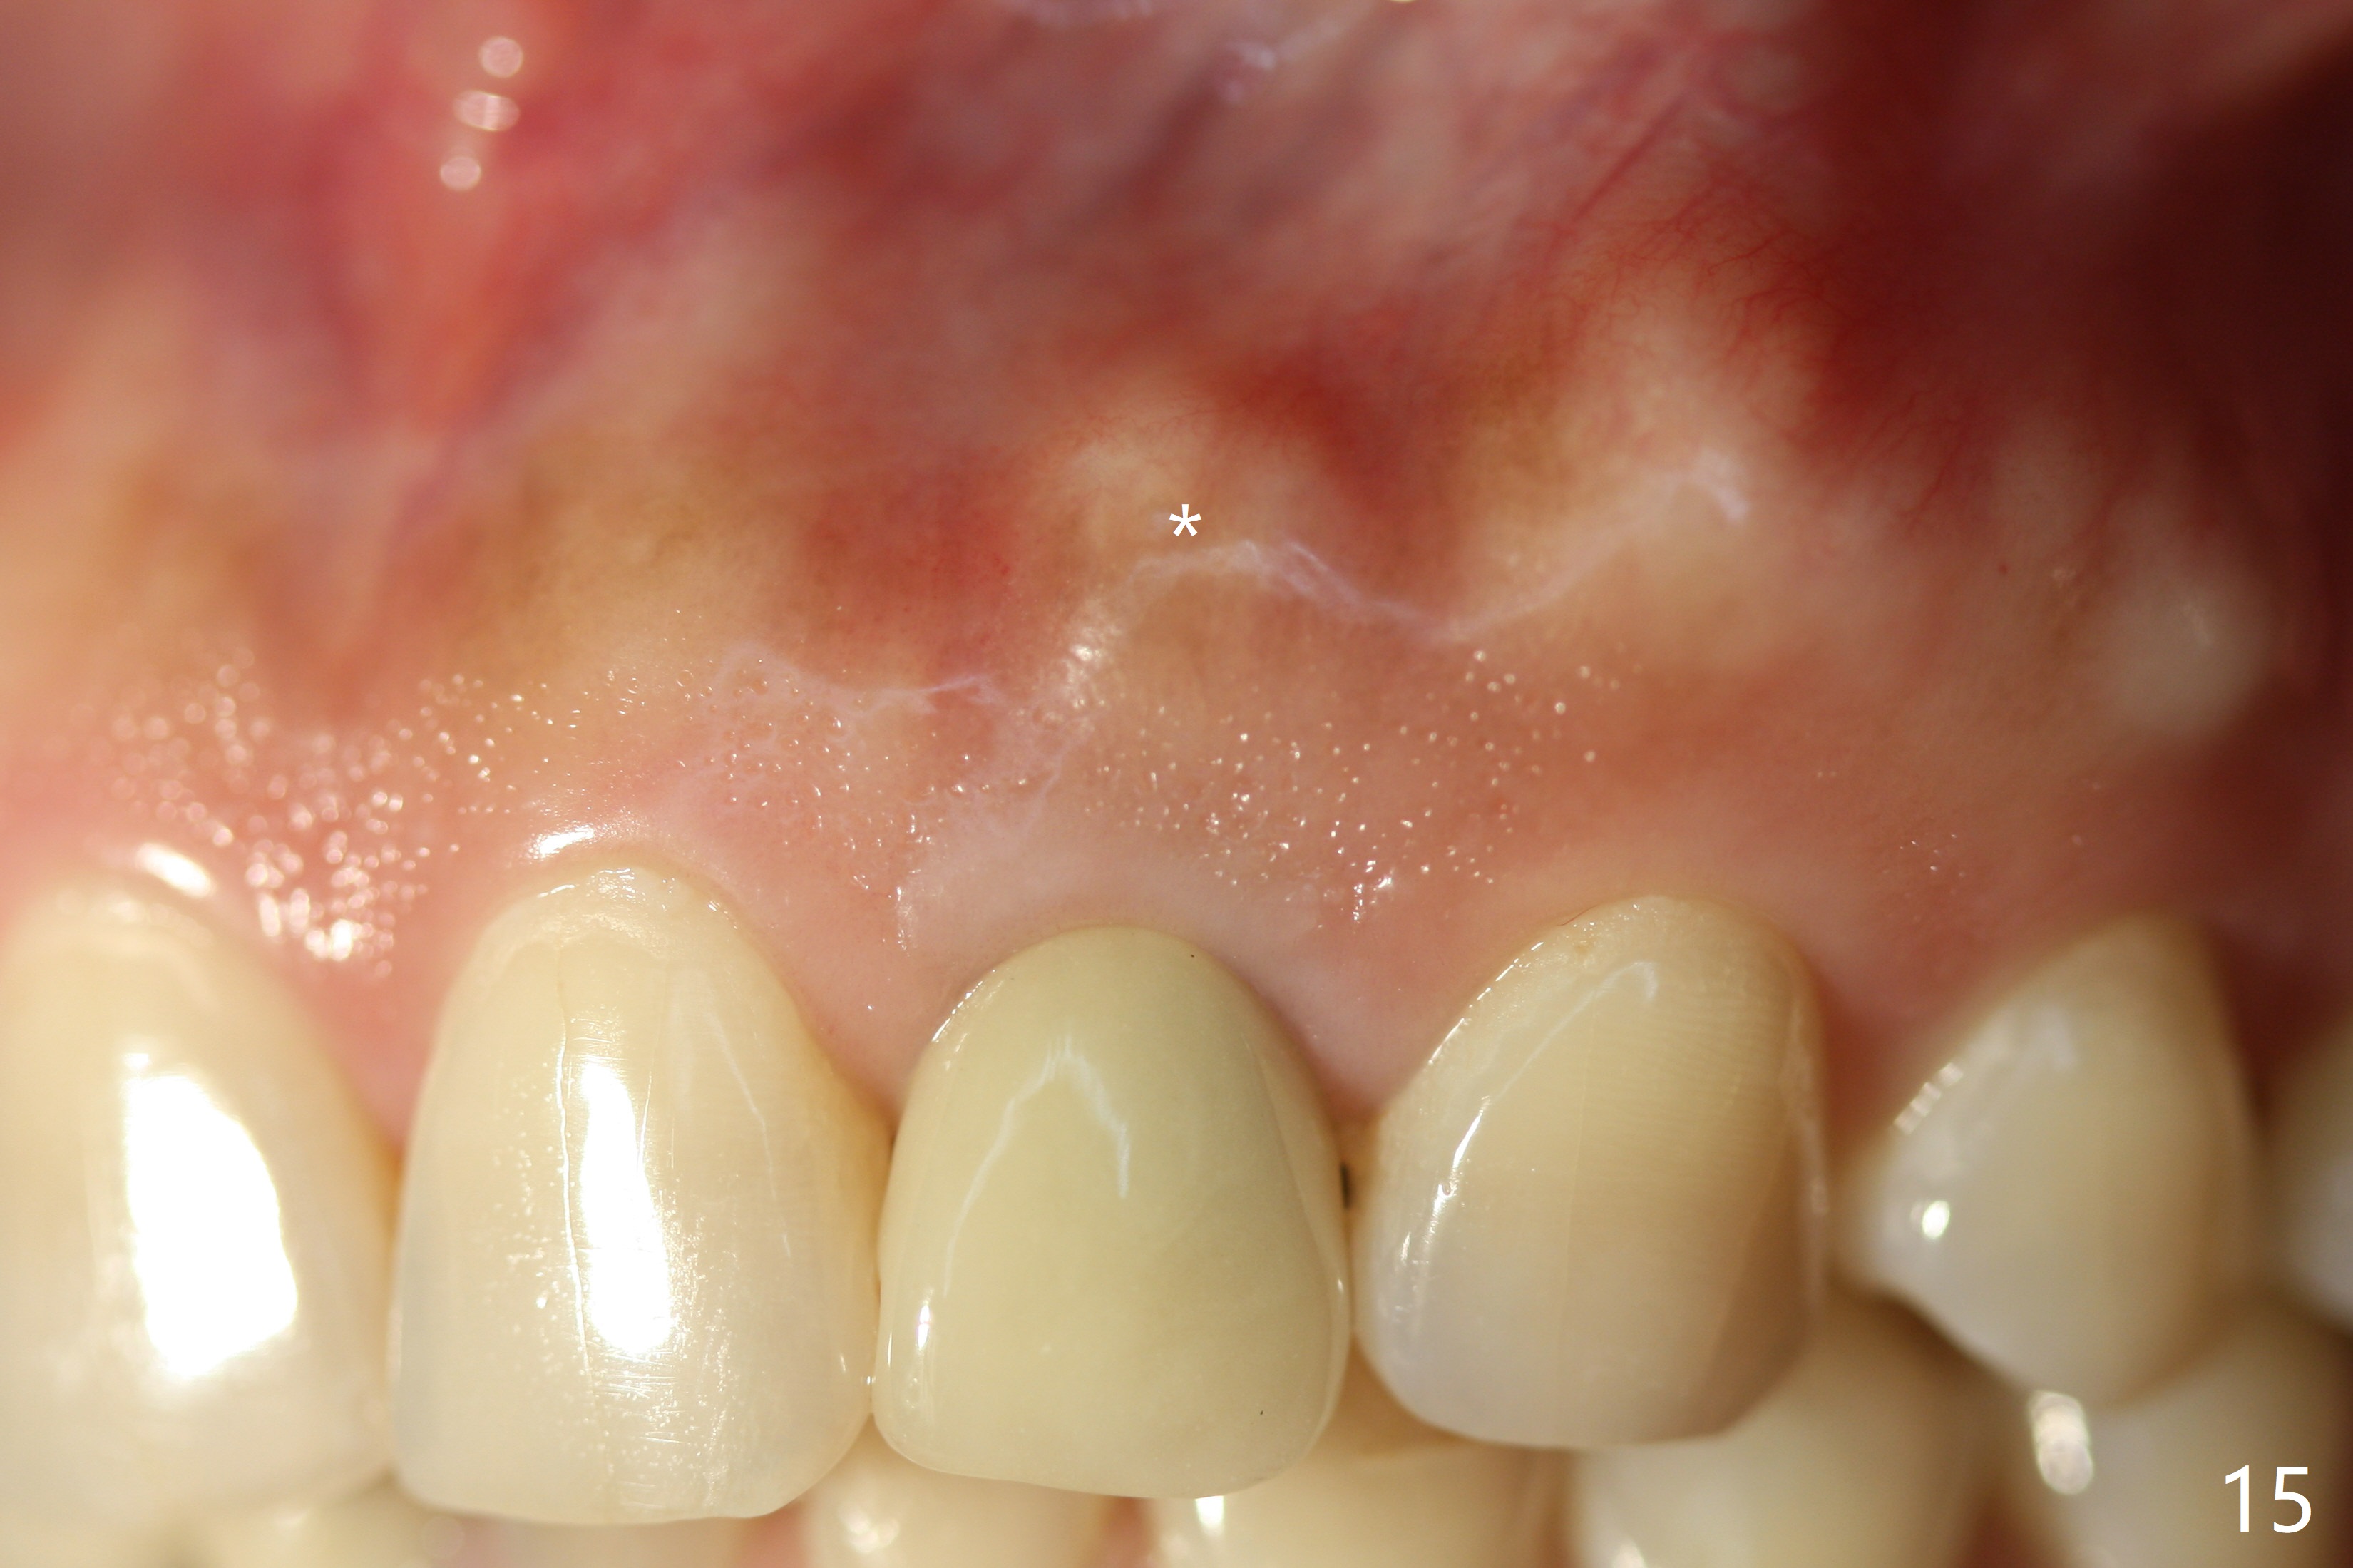

Dense bone forms immediately next to the implant 3 years 5 months post cementation (Fig.13) without gingival recession (Fig.14,15). In fact, the buccal plate maintains root contour over the implant (Fig.15 *). The root prominence remains 6 years 3 months post cementation (Fig.16-18 *). Appreciate the labial concavity associated with implant placement 6 years 9 months post cementation (Fig.19). The implant must have been placed quite palatal.